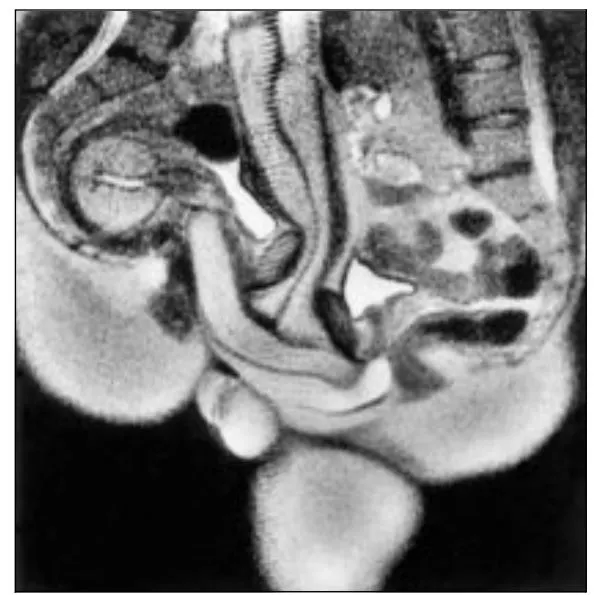

其實過去我們也聊過類似的研究,1999年荷蘭科學家把情侶塞進MRI裡面性交,然後中途喊卡,叫他們停止動作來取影像,發現男性器官並非直直進入,而是中間有個120度角的彎折,證明了「大丈夫能屈能伸」這句話。這個發現讓他們榮獲2000年的搞笑諾貝爾獎。